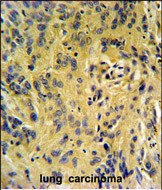

IHC 1/100-1/500 Human,Mouse,Rat

TESC antibodies are widely used in techniques like Western blotting, immunohistochemistry (IHC), and immunofluorescence (IF) to detect tescalcin expression in tissues or cell lines. These antibodies aid in elucidating its tissue-specific distribution, subcellular localization (e.g., cytoplasmic or membrane-associated), and dysregulation in pathological states.